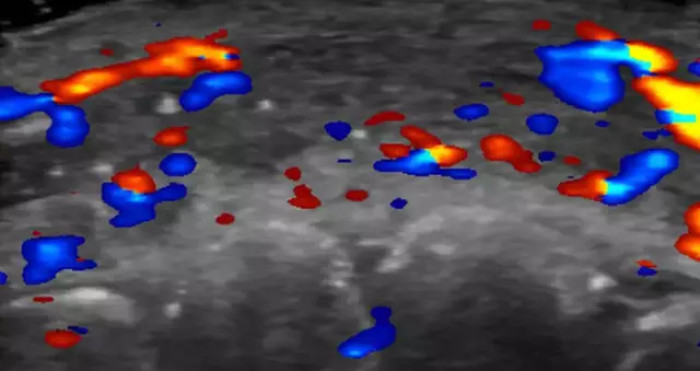

An ultrasound of a patient's lip reveals a section of an artery with no blood flow

An ultrasound of a patient's lip reveals a section of an artery with no blood flowRosa Maria Silveira Sigrist, M.D., and RSNA

Then the ultrasound of a patient’s lip, with a section of artery showing no blood flow, turned “accidental injection” into something you could actually picture.

The scans showing missing blood flow in tiny surface and deeper facial vessels made it clear this wasn’t just a theoretical risk, it was showing up on imaging in real people.

This procedure, however rare, describes filler being accidentally injected into or too near a blood vessel. These scans revealed that blood flow to several tiny vessels related to both surface arteries and those located deeper into the face was absent in less than half of the patients.